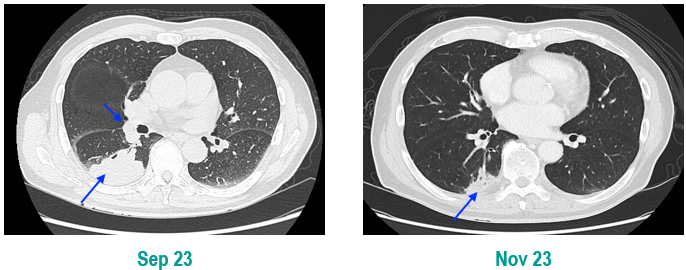

胸部CT显示左侧上叶支气管旁部发现一不规则、边界不清的软组织肿块,大小约为41mm×26mm。增强扫描后,肿瘤呈显著不均匀强化,与肿大的淋巴结粘连且难以区分,部分包裹左上叶支气管,导致管腔狭窄。左上叶肺叶间裂增厚,多个结节灶提示可能存在肺内转移。

治疗缓解评估:影像学(CT)显示原发肿瘤及叶间淋巴结明显缩小;支气管镜显示左上叶开口通畅,原肿块显著退缩,可见白色坏死组织;疗效评估为PR。